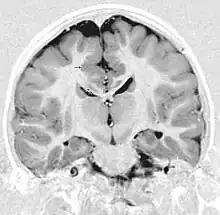

MRI of a child experiencing seizures. There are small foci of grey matter heterotopia in the corpus callosum, deep to the dysplastic cortex. (double arrows)

Grey matter heterotopia is characterized as a type of focal cortical dysplasia. The neurons in heterotopia are otherwise healthy; nuclear studies have shown glucose metabolism equal to that of normally positioned gray matter.[2] The condition causes a variety of symptoms, but usually includes some degree of epilepsy or recurring seizures, and often affects the brain's ability to function.

Detection of heterotopia generally occurs when a patient receives brain imaging—usually an MRI or CT scan—to diagnose seizures that are resistant to medication. Correct diagnosis requires a high degree of radiological skill, due to the heterotopia's resemblance to other masses in the brain.